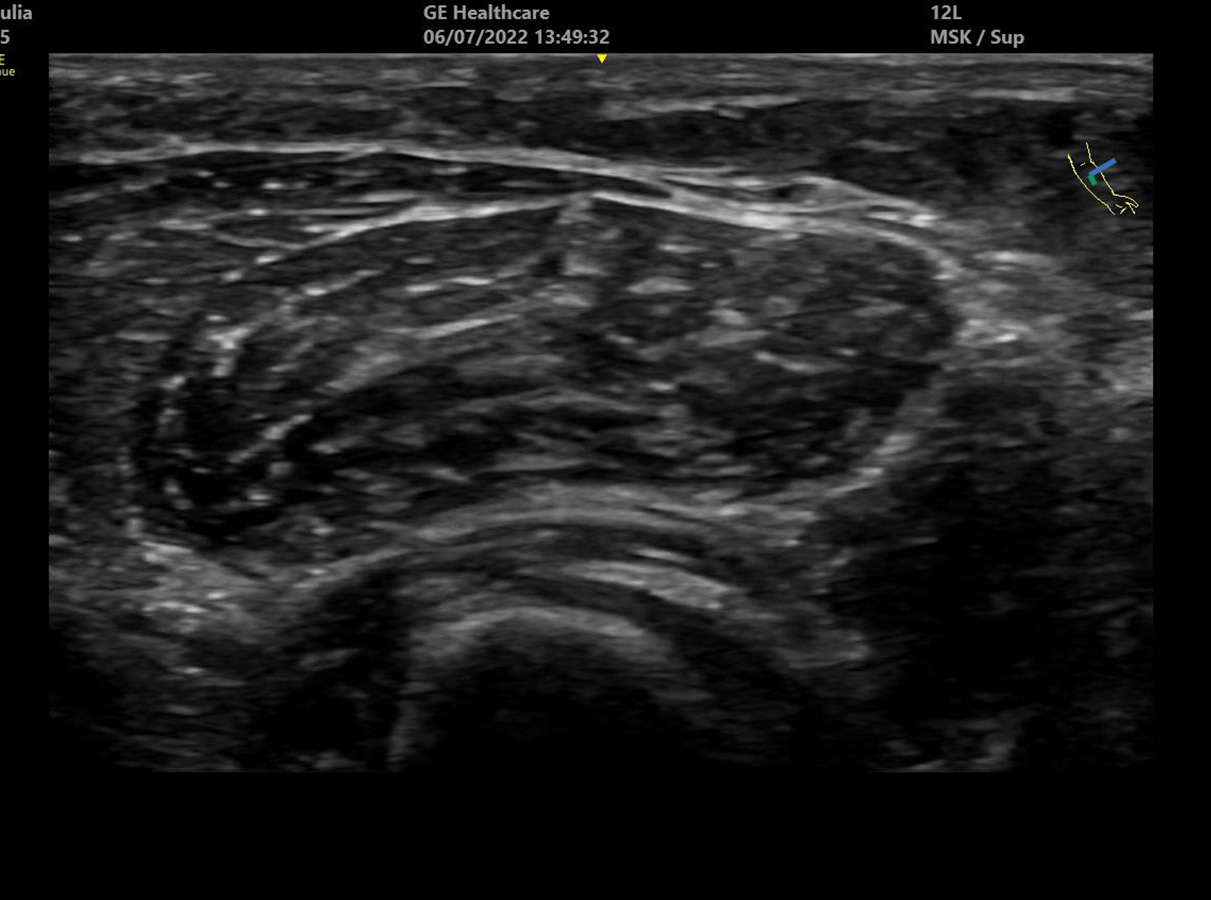

Through focused teaching and practical skill development, you’ll build confidence in image acquisition, optimisation, and interpretation for superficial structures. The module emphasises recognition of normal and abnormal appearances, common benign lesions such as lipomas and cysts, and key red flags for malignancy.

- Recognition of common benign soft tissue lesions: Lipomas, sebaceous cysts, ganglion cysts

- Red flags for malignancy in soft tissue masses

- Identification and differentiation of soft tissue infections (e.g. abscess vs. cellulitis)

You will have access to video materials covering the theoretical content. Didactic teaching will be combined with practical face-to-face sessions, where you will use a range of ultrasound systems to develop scanning skills on normal volunteers. Additionally, simulators will be used to practise imaging and identifying various abnormalities.